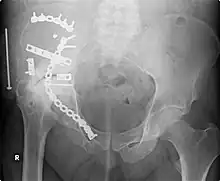

According to applications for board certification from 1999 to 2003, the top 25 most common procedures (in order) performed by orthopedic surgeons are:[22]

- Repair of femoral neck fracture

- Repair of trochanteric fracture

- Hip replacement

- Repair of femoral shaft fracture